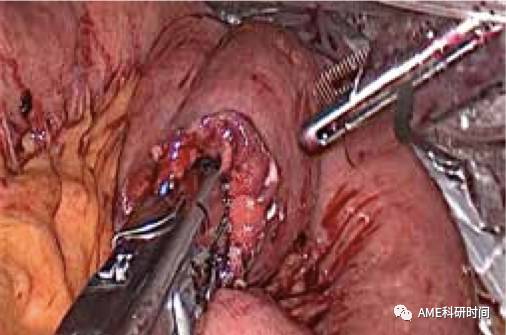

图35 与钉钻头嵌合

注:1)吻合时特别需要助手反向牵拉吻合口输出端肠管(如图36),避免吻合肠管重叠,造成输出肠管钉闭的严重并发症(如图37);2)本步骤中,在腹腔外把空肠套入管型吻合器,并用丝线捆绑也是可行的方法(如图38)。但需要较大的辅助切口、游离过多Roux-en-Y肠袢、手术步骤复杂化,也出现过回纳腹腔时肠管脱落和击发后丝线不能割断的情况。3)采用完全腹腔内置入并管型吻合器(F25号)进行吻合,均可顺利快捷完成。4)吻合完成后,建议放入胃管、或用剥离子通过空肠残端检查吻合口。